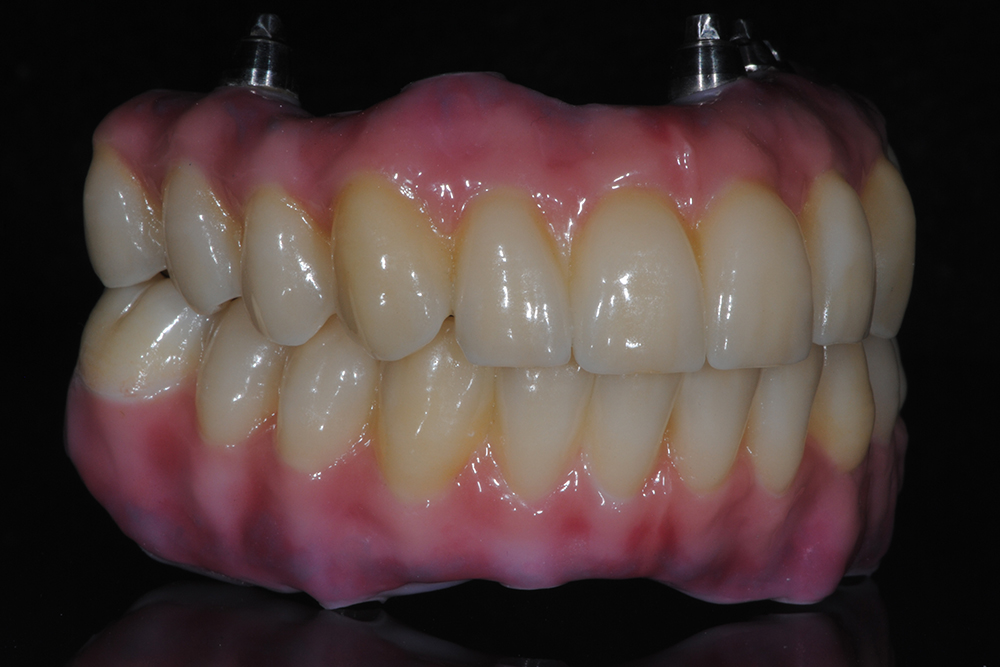

Ripristino dell'arcata superiore ed inferiore su impianti con ricostruzione estetica in zirconia e ceramica Category: Lavori ImpiantiMaggio 9, 2018Condividi questo ProgettoShare with FacebookShare with TwitterShare with Google+Share with PinterestShare with LinkedInProject navigationPreviousPrevious project:Ripristino dell’arcata superiore atroficaNextNext project:Protesi mobile superiore + Overdenture inferiore